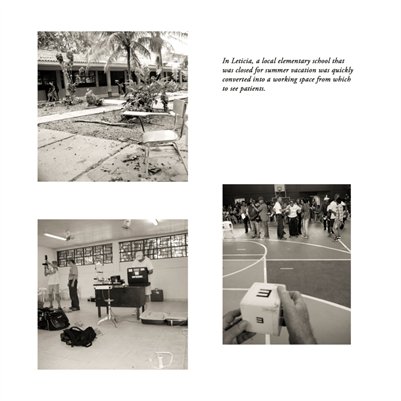

Darkness into the Light. In 2012, The Amazon Project gave eye care to nearly 6000 patients within a 200 kilometer radius of their base in Leticia, Colombia.